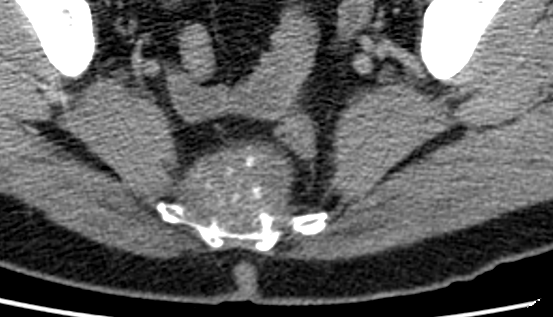

- Se trouvent sur tout le squelette axial mais Sacro-Coccygien et Base du Crane ++

- Très hyperT2 avec prise de contraste

- Destruction osseuse alentour

sacum coccyx chrodome sacré sacrum sacral presacré présacré présacram